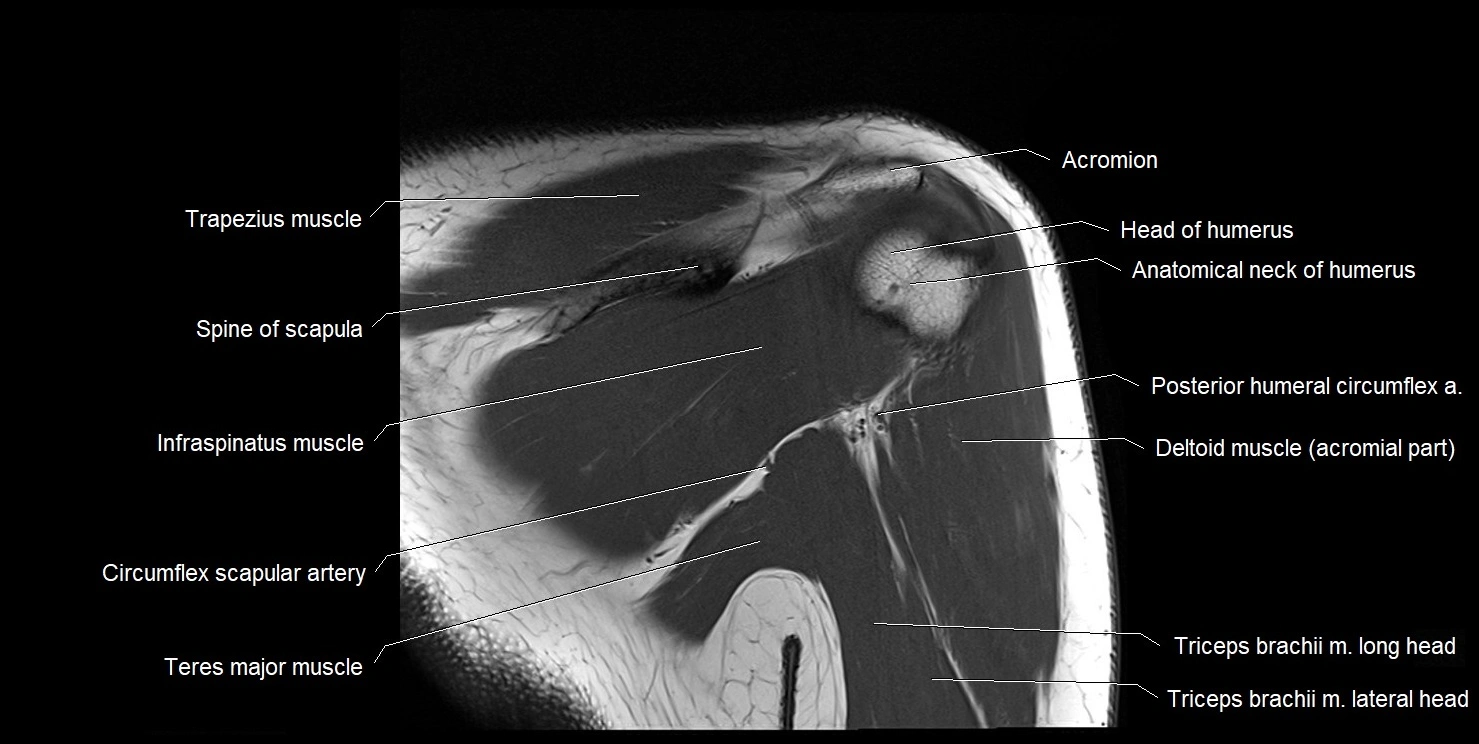

Fullscreen Image